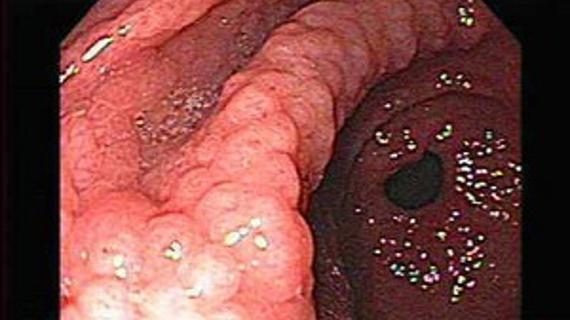

Гастроэнтерология